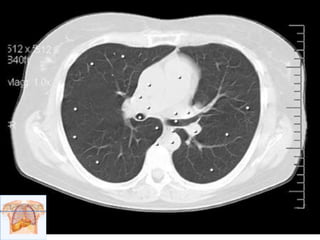

Ventana pulmonar

1- Bronquio segmentario

posterior del lóbulo superior

derecho.

2- Bronquio segmentario

anterior del lóbulo superior

3- Bronquio derecho.

4-Bronquio izquierdo.

5- Lóbulo superior

izquierdo.

6- Lóbulo inferior izquierdo.

Flecha roja, Fisura oblicua

(mayor).